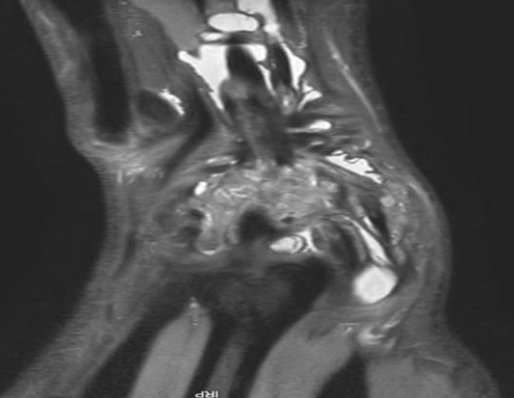

5. Diagnostic d’une arthropathie digitale destructrice

Catherine Phan

– SLAC – SNAC – SCAC